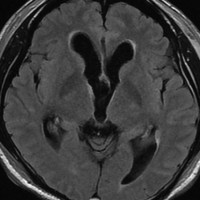

CTでは壁が厚く高密度,MRI T2強調画像では低信号,T1強調画像では高信号です。内部に血液を含んでいるようなのう胞に見えます。のう胞の壁は非常に厚く硬いものが予想されます。閉塞性水頭症になっています。

若い男性ですが,内視鏡手術では摘出できない壁がガチガチのものでした。モンロー孔が広いので経脳梁到達法 transcallsal approachで手術しました。右前頭部から入ろうとしましたが,架橋静脈のために入れず,左前頭葉を除けて,透明中隔の正中に達しました。ところが,左の脳弓が菲薄化して広がり腫瘍の上面にみえましたから,左のモンロー孔からは摘出できませんでした。しかたがないので,右のモンロー孔から腫瘍を摘出しています。腫瘍の周囲には第3脳室脈絡叢が広範囲に癒着していました。のう胞内容は暗褐色の古い血腫でした。のう胞の壁は硬く厚い結合織で肉芽腫のような肉眼所見でした。左右の脳弓にも癒着し,内大脳静脈にも癒着していたので,その部分には皮膜を残しました。

術後のMRIです。幸い,記憶障害などの脳弓症状はでませんでしたが,かなりリスクの高い手術でした。